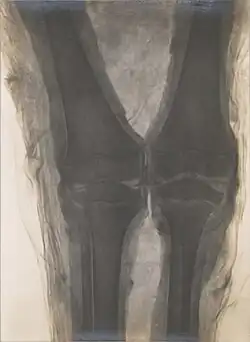

In addition to sources by ancient writers and modern scientists, a better understanding of the Ancient Egyptian mummification process is promoted through the study of mummies. The majority of what is known to be true about the mummification process is based on the writing of early historians who carefully recorded the processes—one of whom was Herodotus. Now, modern day archaeologists are using the writings of early historians as a basis for their study. The advancement of new technology including x-rays has allowed for the analysis of mummies without destroying the elaborate outer wrappings of the body. In addition to the use of x-rays, autopsies are also being performed in order to gain a better understanding of the diseases suffered by Ancient Egyptians as well as the treatments used for these diseases. A pregnant mummy sheds light on pregnancy complications and prenatal care and treatments.[50][51] In learning their age of death, experts are able to create a timeline of the dates regarding the ruling of Egyptian kings. In looking at the bones of the mummified bodies, experts get a better idea of the average height and life span. Studying Ancient Egyptian Mummies, archaeologists are able to learn about the past.